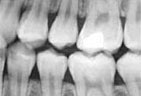

We use state of the art digital X-rays and digital cameras to help with an accurate diagnosis of any concerns. Digital X-rays use less radiation to get a diagnostic picture of your teeth and they help the environment by eliminating the use of chemicals to process the film.